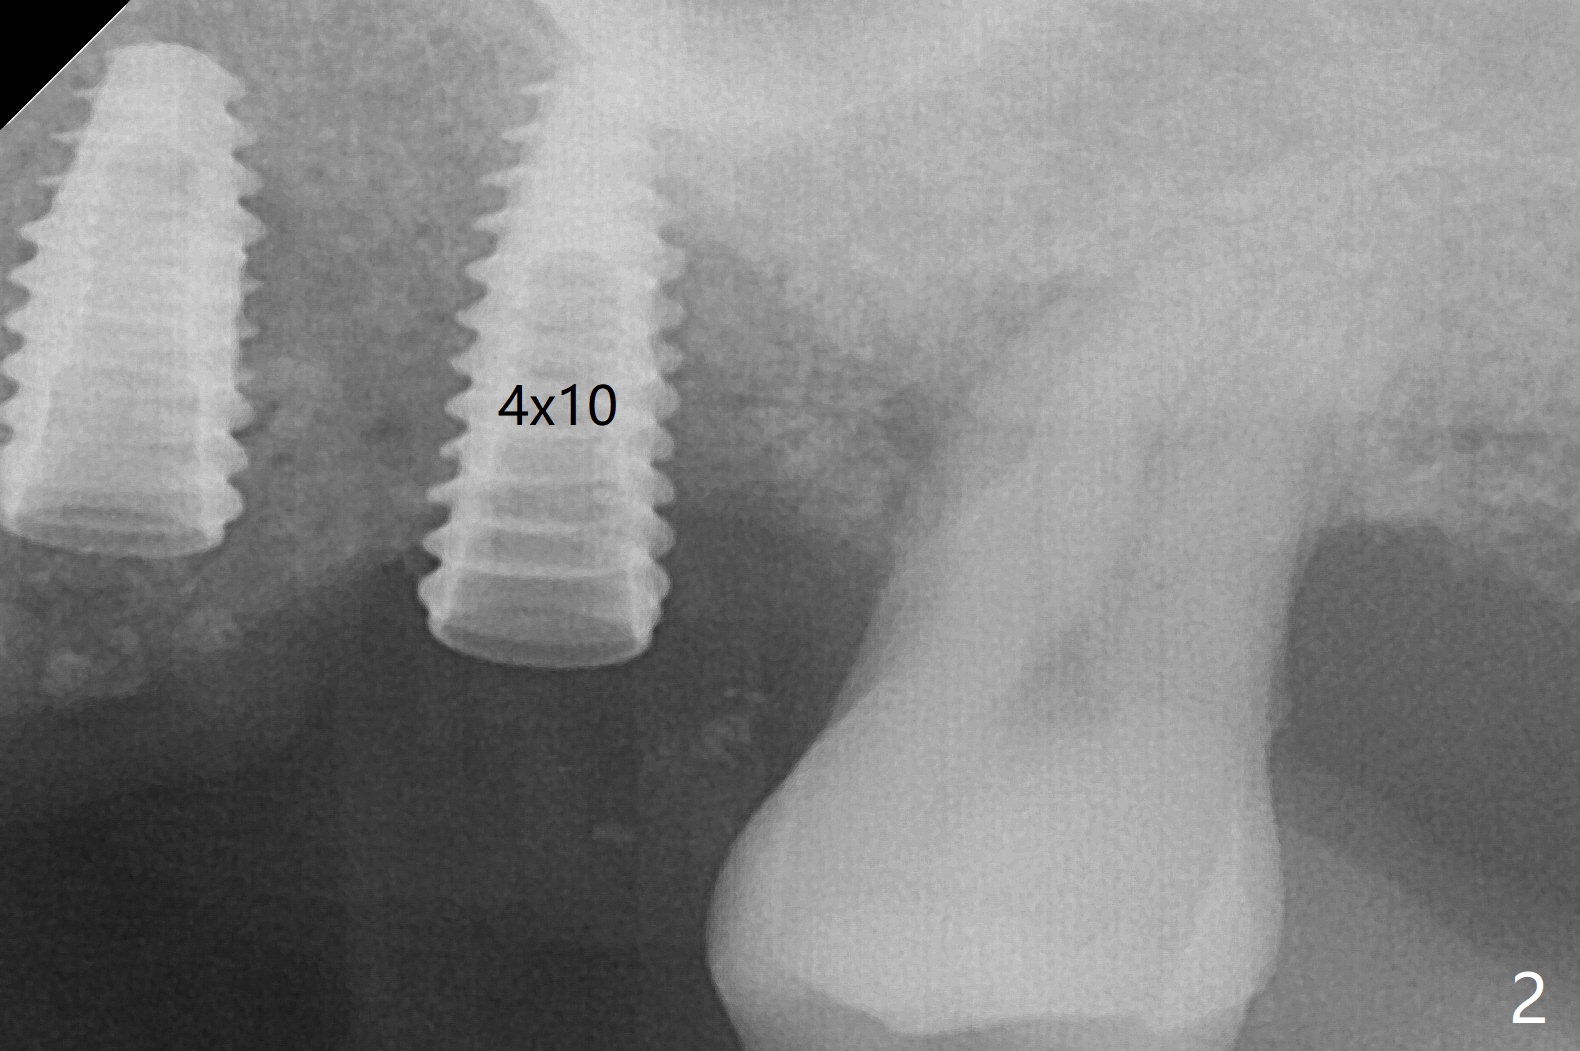

左上六植牙第三次失败后五个月,牙槽嵴宽度尚可,切开后放置导板,3.2乘19毫米园钻头好像接近上颌窦底板(图一),但是粘性骨块和4乘10毫米报废植体就不能进入上颌窦(图二),最后不得不使用3毫米Bicon骨凿,之后同一个报废植体就似乎进入上颌窦(图三),4.5乘8.5毫米正式植体植入深度和稳定性均正常(图四),腭侧植体稍微暴露,放置愈合螺丝后,放置骨粉和PRF膜,缝合,左上5植体放置5.7x4.5(4)毫米基台,固定牙周敷料。术后5.5个月植体好像整合(图五),缺牙间隙特别小,5临时牙冠(P)必须取出才能切开暴露植体,放置5.5x5毫米愈合基台(图六)。伤口愈合后,必须做渐进性负荷,之后做简单局部矫正,推7往远中,6缺失3年,7往近中倾斜移位。两周后牙周敷料脱落,伤口愈合,放置修复基台,故意将基台平面朝远中,足够空间制作临时牙冠(图七)。调整基台长度(比较图七,八)。制作连体牙冠(5,6),有意提高5牙冠高度,使左上7不与对合牙接触,有利于远中移位(图九)。也要在对侧提高咬合(图十)。局部矫正一个月后,磨去右侧咬合垫和磨短左上5,6临时牙冠,前牙还不能完全接触(图十一)。1-2星期前牙开合自行消失,取模做左上5,6牙冠。局部矫正似乎使左上7远中移位大约3毫米(比较图十二,十三)。粘固拧紧后(20 Ncm)14号牙牙冠咬合增高,拍摄根尖片(图十三),两个基台好像仍然完全就位,然后调整咬合。